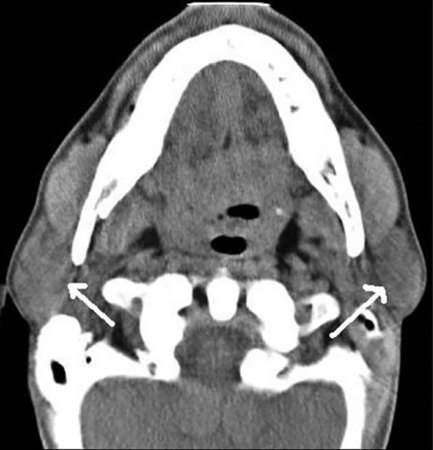

Saliva production is highest during the day, especially at mealtimes. About 99 percent of that goo is water. The rest is mostly proteins and salts. Most of our spit comes from three major pairs of salivary glands: one pair under the tongue, another pair beneath the jaw and a third pair near the back of the jaw and in front of the ears. Many minor glands secrete saliva, too. Tissues lining our mouth and the plasma in our blood add tiny amounts of material to all that saliva. The plasma gets in where teeth jut out at the gums, Ruhl explains.